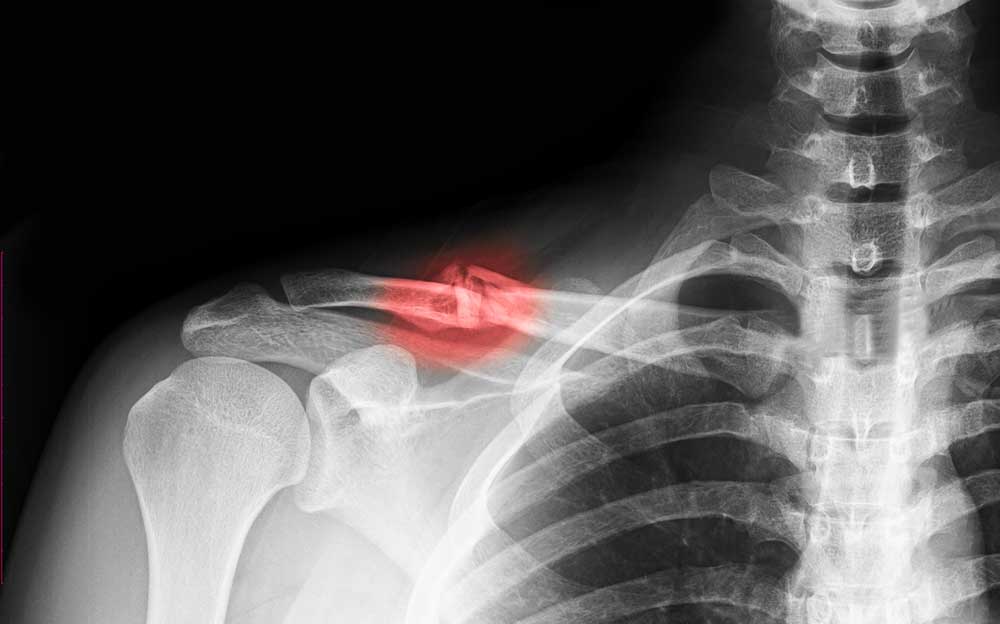

Types Of Clavicle Injuries . a clavicle fracture is a break in the collarbone, one of the main bones in the shoulder. — midshaft clavicle fractures are common traumatic injuries caused by a direct impact to the shoulder girdle and is. a broken collarbone is a relatively common injury, especially in kids. A fall or a blow to your shoulder can fracture your collarbone. — although least common among the different clavicle fracture types, acute proximal fractures are most often. — the differential diagnosis of a clavicle fracture includes acromioclavicular joint injury, rib fracture, scapular fracture, shoulder. This type of fracture is fairly common, accounting for about 5% of all adult. The collarbone, also known as the clavicle, connects the shoulder blade to the breastbone. — a broken collarbone is a common injury. — distal clavicle fractures are traumatic injuries usually caused by direct trauma to the shoulder from a fall in.